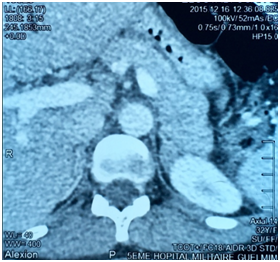

E.O. was a 31-year-old female, with a history of celiac disease under gluten-free diet, and a pregnancy-induced hypertension one year ago, without having been screened for secondary hypertension, to the best of our knowledge. A satisfactory blood pressure (BP) has been reached under treatment with nicardipine (100mg/day). The patient was admitted to our hospital because of headache, muscle weakness and heart palpitations, for two weeks. On physical examination, the patient was in regular general condition and with a healthy coloring. Her weight was 53.5 kg and height 162 cm (BMI=20.41Kg/m2). Blood pressure measured with a manual armlet 190/110 mmHg, heart rate 100beats/minute and regular, respiratory rate 18cycles/min, body temperature 36.9°C. On auscultation, her lungs were clear with no rales. Her heart auscultation showed regular cardiac rhythm with cardiac sounds of normal intensity and no murmurs. Her lower limbs showed symmetric palpable pulses and no edema. The power and sensation of both lower and upper limbs were normal. The abdominal examination showed hydro-aerial noise, no visceromegaly and no abdominal murmur. Thyroid gland examination was normal. There was neither obesity nor hirsutism. Other physical examination was normal. Laboratory findings were as follows: serum potassium 1.68mEq/L (normal range (NR)= 3.5-5.1), sodium 143 mEq/L (NR=136-145), alkaline reserve 32mEq/L(NR=22-31), corrected calcium 95mg/L(NR=86-100), phosphorus 29.9mg/L (NR=25-45), urea 0.15g/L (0.13-0.45), creatinine 3.9mg/L(NR=5-9). The complete blood count and coagulation indices were normal. The thyroid function test was normal (0.94mU/L; NR=0.27-4.2). The measurements of sodium and potassium in the 24-hour urine were 54mEq/L (NR=54-190) and 63 mq/L (NR=25-125), respectively. The ECG showed presence of changes of hypokalemia, U waves and no hypertension changes. Echocardiography assessment of hypertension was negative, and there was no hypertension retinopathy. She was treated with boluses of intravenous potassium chloride and oral potassium supplements, for 260 mmol/day over 6 days. Initially her hypertension was treated with intravenous nicardipine utilizing an electrical syringe pump. Despite intravenous and oral potassium supplementation, her serum potassium level remained low. The PA was suspected because of persistence hypokalemia in association with hypertension and alkalosis. However, after correction of serum potassium level, the patient was examined for the plasma aldosterone concentration (PAC) and direct rennin concentration (DRC). Results revealed a low DRC level of 0.9mUI/L (NR=2.8-39.9), along with a very high PAC level of 2613pmol/l (NR=83-405). The aldosterone to rennin ratio (ARR) was 523pmol/l per mUI/l (N<64). Subsequently, after a three-day oral sodium load, 24-hour urine was tested for the concentration of sodium (260mmols) and aldosterone (27.3mg). Abdominal computerized tomography (CT) revealed a 28x21 mm hypo-dense mass (1UH of density), not enhanced by the contrast product, over the left adrenal gland (Figures 1) (Figures 2). After using spironolactone 100 mg/day and nicardipine 150 mg/day for one month preoperatively, the BP normalized (BP=125/85 mmHg), the headache, weakness and heart palpitations significantly improved, and the serum level of potassium was 4.5 mEq/L. Therefore, the patient underwent a successful laparoscopic left adrenalectomy (Figure 3), and the postoperative course was well. The macroscopic tumor consisted of an ovoid piece of yellow color tissue with weight: 28gr, circumscribed mass: 20x30mm in dimensions adjacent to adrenal tissue. Histologically, the adrenal mass showed an encapsulated epithelial neoplasia with cells of clear cytoplasm, round nuclei and conspicuous nucleoli. However, necrosis, capsular invasion and atypical mitosis were not found (Figure 4). The anatomic pathological diagnosis was adenoma of the adrenal gland consistent with Conn’s adenoma. The patient was normotensive and serum potassium was 4.5mEq/L without any antihypertensive medication or supplement for the last three months after discharge. She was stable with a optimal control of blood pressure without hypokalemia with a 2-year follow-up.

Concerning therapeutic approach, the goal is the prevent the morbidity and mortality associated with hypertension, hypokalemia and cardiovascular damage.17 The cause of the PA helps to determine the appropriate treatment. Normalization of blood pressure should not be the only goal in managing a patient who has PA. In addition to the kidney and the colon, mineral corticoid receptors occur in the heart, brain and blood vessels. Excessive secretion of aldosterone is associated with increased risk of cardiovascular disease and morbidity. Therefore, normalization of circulating aldosterone or mineral corticoid receptor blockade should be part of the management plan for all patients with PA.17 Unilateral laparoscopic adrenalectomy is the preference treatment for patients with APA, and bilateral hyperplasia should be treated with mineral corticoid antagonists: spironolactone or eplerenone. Cardiovascular morbidity caused by aldosterone excess can be decreased by either unilateral adrenalectomy or mineral corticoid antagonist. Our patient was treated with laparoscopic left adrenalectomy after using spironolactone 100mg/day and nicardipine 150mg/day for one month preoperatively, leading to correction of hypokalemia and optimal control of blood pressure.